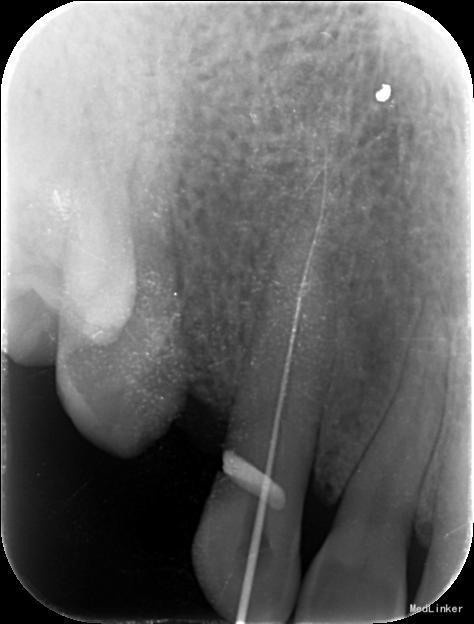

诊断:13慢性根尖周炎 治疗计划:13根管治疗后冠修复 治疗:1. 13去腐,腭侧开髓暴露髓腔,降牙合,探查根管,干燥根管,电测工作长度WL=25mm,此时根尖区探痛明显,按此长度插针拍片示超出根尖孔4mm,推算出WL=21mm。EDTA下,常规预备至35#,3%过氧化氢和生理盐水冲洗+超声荡洗根管交替进行。隔湿,干燥根管,封CP棉球, 氧化锌水门汀暂封。嘱勿用患牙咬物。 2.主诉:右上前牙上次治疗后后无不适。 检查:13暂封物在,叩痛(-),牙体无松动,牙龈未见明显异常。 处置:13去除暂封物,生理盐水冲洗并干燥根管,试尖到位,进口根充糊剂+牙胶尖冷侧压根管充填,氧化锌水门汀暂封,术后拍片示:13根充恰填。嘱勿用患牙咬物。 建议:13冠修复

根管治疗的关键是彻底清洁根管系统,对根管进行严密的充填,根管充填的止点是根尖狭窄处,即牙本骨质界,此处是解剖学和组织学牙髓末端及牙周组织的起始点,器械一旦超出牙本骨质界,就会对根尖周组织造成创伤,并将炎症带入根尖周组织。因此,在根管预备前,准确测定工作长度非常重要。 工作长度是指从牙尖至牙本骨质界之间的距离,它不同于牙的长度。 牙长度为切缘或牙尖至解剖根尖之间的距离。 临床上常用的方法有电测法、X 线辅助计算法,根尖定位仪借助于根管内部阻抗的规律性变化对其工作长度进行测量,准确性强,且应用简单方便,能够对根尖已经完成发育的牙根准确的测定其根管工作长度。但该方法亦具有一定局限性,如对戴有心脏起搏器患者严禁应用,同时期准确性也会因根管内外某些因素而受到干扰。X 线辅助测量通过将根管及根尖区域进行二维成像,在平面影像上确定根管长度,但这种平面影像只能分辨牙本质- 骨质界,而当根尖区不清晰时则无法准确判断根尖狭窄所在。同时这种方法测量准确性与拍摄技术、选用方法均有一定关系。 本病例先是通过根尖定位仪测量工作长度,但是在根尖定位仪显示至根尖狭窄时,长度为25mm,此时患者疼痛明显,按此长度摄插针X片,显示超出根尖孔4mm,推测出实际工作长度为21mm,按此长度预备后根管充填显示恰填。分析电测法出现误差的原因可能有两种,一是牙齿颈部的重度楔状缺损以及电解液的冲洗等可导致测量电流发生颈漏, 而使测量值不准确;二是由于根尖区牙槽骨受到破坏而导致骨小梁稀疏,锉尖在从根尖孔穿出后无法探及根尖处牙槽骨,而穿出一段距离后与根尖外部牙槽骨相接才形成回路,此时测量仪才会认为探及根尖而显示数值,故所得数值偏大。 目前, 根尖定位仪在临床应用上还是比较稳定的,在大多数的病例中定位根尖止点的准确性较高, 但是也会受到电解质、龈下龋、根折、根尖孔粗大和根尖未成形等因素的影响, 可能会产生错误结果,此时仍然需要X 线摄片的辅助。因此在使用根尖定位仪的过程中要注意, 当遇到一些特殊的情况时, 结合X 线照片法可以提高测量根管工作长度的准确性,此外,X 线片对牙体、牙周等组织情况均可以提供直观的影像,这对临床诊治具有十分重要的作用与意义。